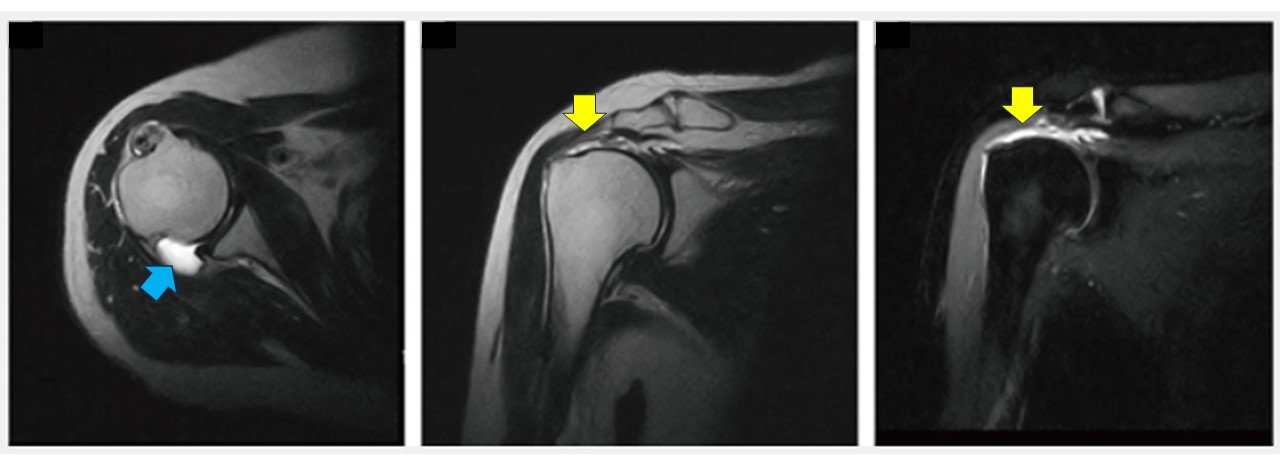

下の画像は、右肩のMRI画像になります。青色の矢印は、肩関節の水の溜まり、黄色の矢印は腱板が痛んで部位を指しています。